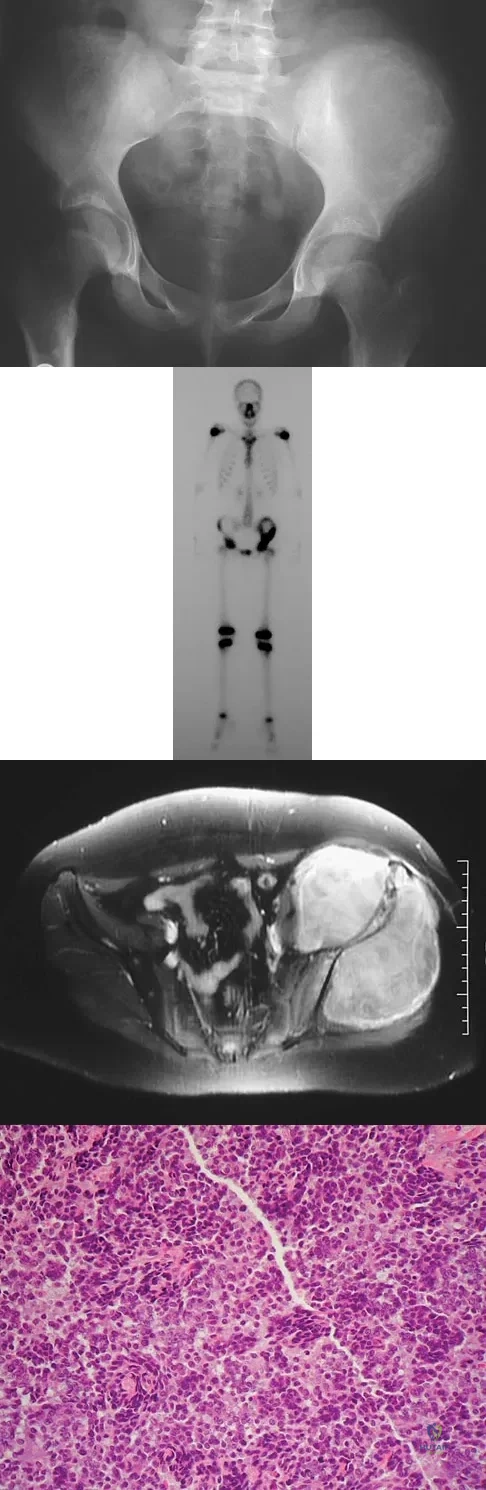

Question 39

A 13-year-old girl has had increasing left hip pain for the past 4 months. A radiograph, bone scan, MRI scan, and photomicrograph are shown in Figures 1a through 1d. Which of the following immunohistochemistry results would confirm the most likely diagnosis?

Explanation